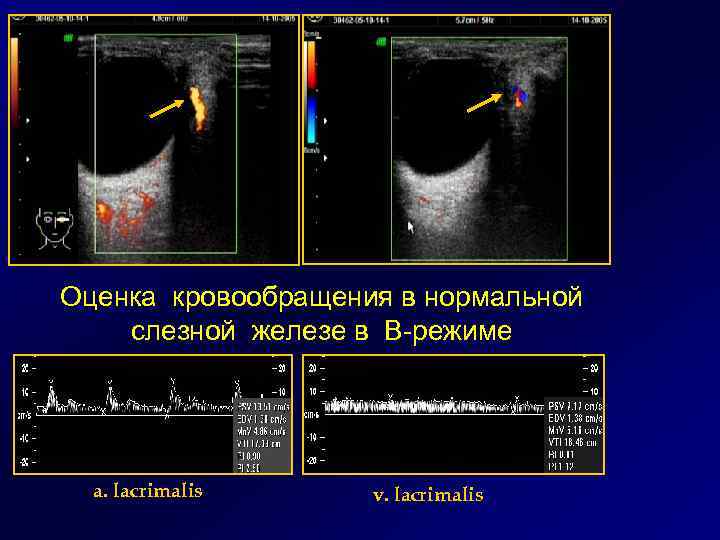

Оценка кровообращения в нормальной слезной железе в В-режиме a. lacrimalis v. lacrimalis